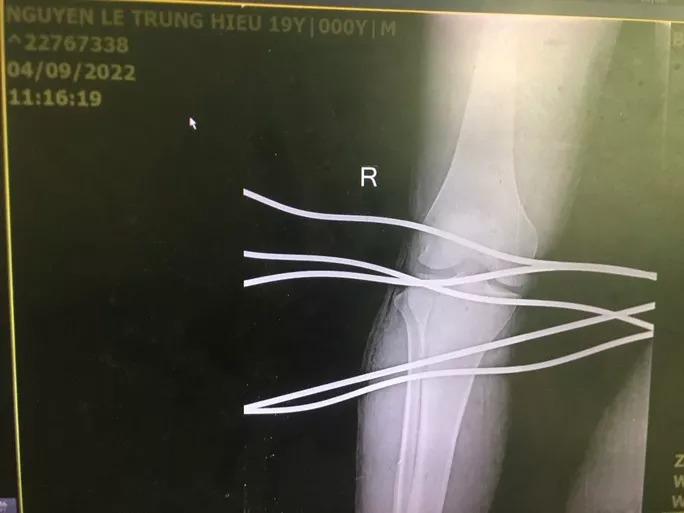

Hình ảnh chụp phim cho thấy 5 thanh sắt đâm xuyên qua chân nam thanh niên